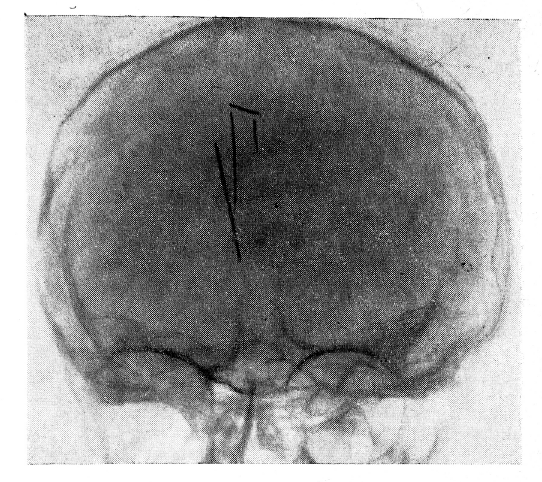

Рис. 1

Рентгенография от 17/IV-59 г. (рис. 1 и 2). На рентгенограмме черепа в двух проекциях определяются две швейные иглы, располагающиеся почти вертикально, внутри мозговой ткани — в области венечного шва и на полсантиметра вправо от срединной сагиттальной плоскости. Верхние концы игл (с ушками) располагаются вблизи от внутренней пластинки свода черепа. Длина игл — около 5 см. В этом же отделе черепа под углом к описанным иглам располагаются два отломка игл с заостренными концами длиною около 1,5 см. Костных дефектов в своде черепа не найдено.